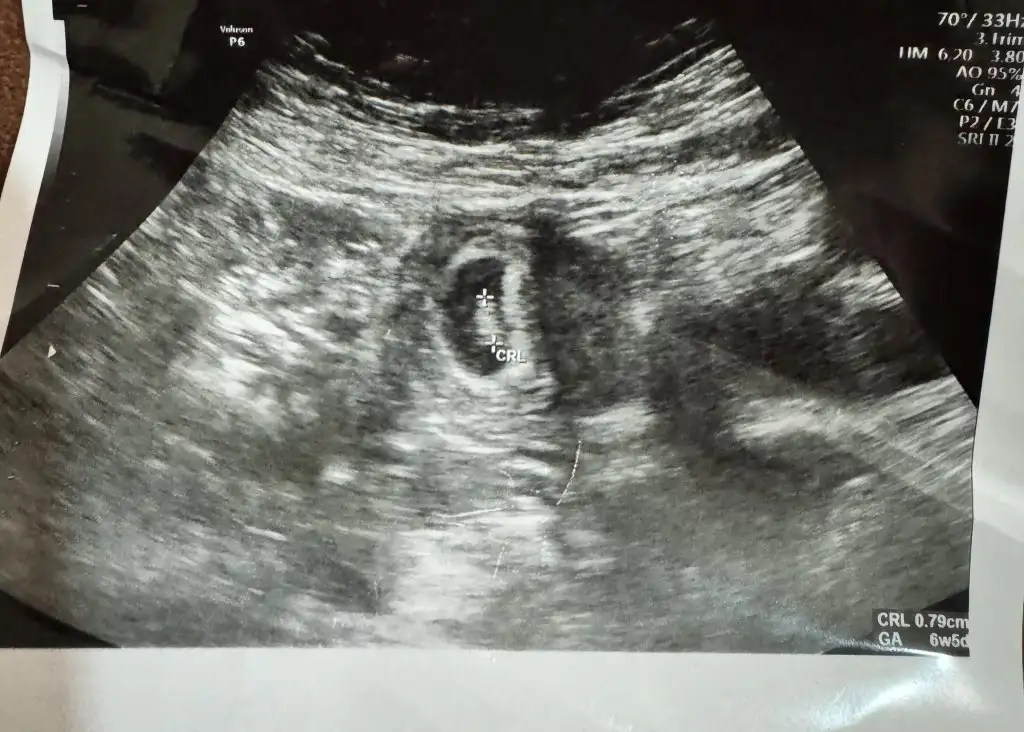

5 ve 14. haftaya kadar olan ultrason fotolarınızı paylaşın. Vajinadan mı yoksa karından mı çekildiğini ve kaç haftalık olduğunu da mutlaka belirtin.

Bana da bakabılır mısınz 7+6 karın usgKıza benzettim sağlıkla gelsin

Bende çok merak ediyorum 5 haftalık karından ultrason fotosu

Merhaba benim içinde bakarmisiniz karından ultrasonSelam Kızlarbir çok kişi gruplardan beni bilir. Yine yetiştim imdatlara